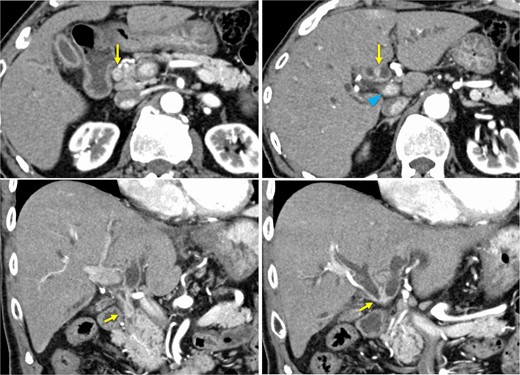

Bone marrow biopsy revealed a normal myeloid/erythroblast ratio and a slightly increased number of megakaryocytes without platelet adhesion (Fig. 2), consistent with ITP. The possibility of ITP secondary to pCCA was considered. Prednisolone therapy was initiated at 25 mg/day (0.5 mg/kg/day), with gradual dose reduction based on platelet response (Fig. 3). Lansoprazole 15 mg medication was also initiated for steroid ulcer prophylaxis.

Bone marrow biopsy specimen (Naphthol AS-D chloroacetate esterase Giemsa staining, ×400). The myeloid/erythroblast ratio is normal, and the number of megakaryocytes is slightly increased without platelet adhesion.